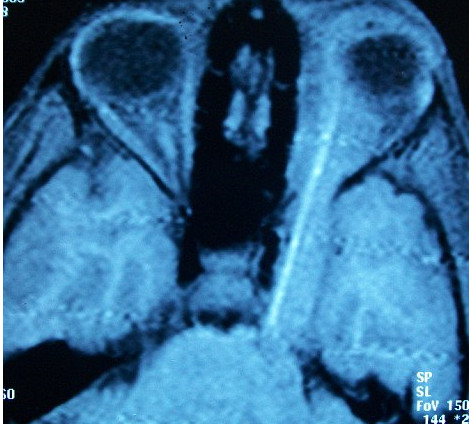

A invins moartea, desi are doar 11 ani! Este vorba despre un baietel din India, Rahul Devi, care traieste de doi ani cu un bat de 10 cm infipt in ochiul stang, chiar sub spranceana, dupa o partida de joaca cu prietenii.

Baiatul a scapat de cosmar abia dupa ce parintii l-au dus la un spital din Delphi. Aici, medicii au reusit sa extraga batul din ochiul baiatului in urma unei operatii de sase ore.

Doctorii au fost uimiti de faptul ca baiatul a supravietuit intrucat batul ii penetrase creierul.

"Este un miracol. Toate zonele principale din creier au fost afectate de tepusa, dar nu au existat complicatii. Este foarte curios cum de nu s-a infectat zona. Acest baiat a avut un noroc teribil", a recunoscut medicul, care insa nu i-a putut salva si vederea in partea stanga.